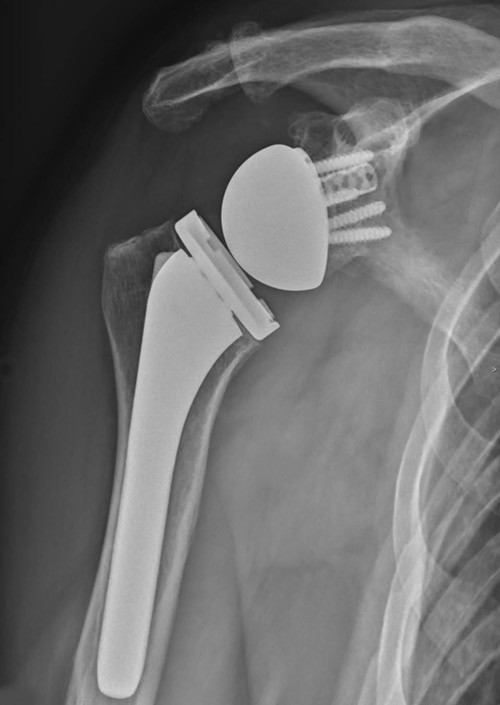

Prothèse totale de l’épaule

La prothèse totale de l’épaule consiste à remplacer les surfaces articulaires abîmées par des implants artificiels.

Arthrose avancée, douleurs importantes et perte de mobilité impactant la vie quotidienne.

Soulager la douleur et restaurer une fonction satisfaisante de l’épaule.

La récupération est encadrée par une rééducation adaptée. Les résultats sont généralement très satisfaisants sur la douleur.